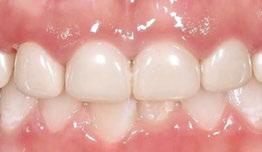

Case 2

A 3-year-old female presented with pulpal necrosis and abscess on #E and pulpal necrosis on #F. Extraction therapy or pulpectomy was offered. The family was highly motivated to retain #E and #F. The pulpectomy was performed with 0.02 K-Flex hand files, 3% NaOCl with a lateral vented needle, obturated with Vitapex (Neo Dental International Inc., Federal Way, Washington), a premixed paste of calcium hydroxide and iodoform. The access was filled with a HVGIC sealing the pulp therapy and increasing the clinical success by minimizing the potential for bacterial contamination. NuSmile ZR anterior crowns were selected as offering a full-coverage, esthetic, cemented restoration with no polymerization shrinkage when compared to a composite restoration. Crowns were cemented with NuSmile® BioCem (NuSmile, Houston, Texas). This is clinically beneficial as the provider would want to cement a restoration that provides limited microleakage minimizing the potential for bacterial contamination.15-17 At 6-month follow up, lesion healing had occurred with healthy gingival margins and no plaque accumulations (Figure 3).

Figure 3: NuSmile® ZR Crowns were selected as a cementable full coverage restoration. At 6-month recall, apical tissues were healed with excellent gingival health Figure 4: SMART style restorations that were definitively restored with NuSmile® ZR Crowns as an esthetic option to cover SDF staining